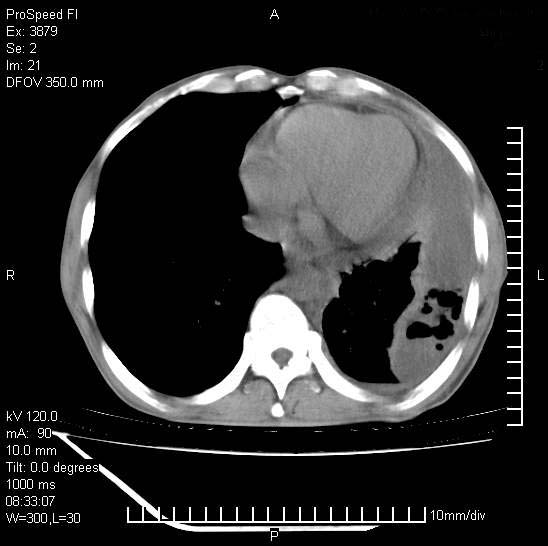

以下是引用37度在2008-6-6 11:20:00的发言:[br]1.包裹性积液,多考虑结核性;[br]2.穿刺术后改变。